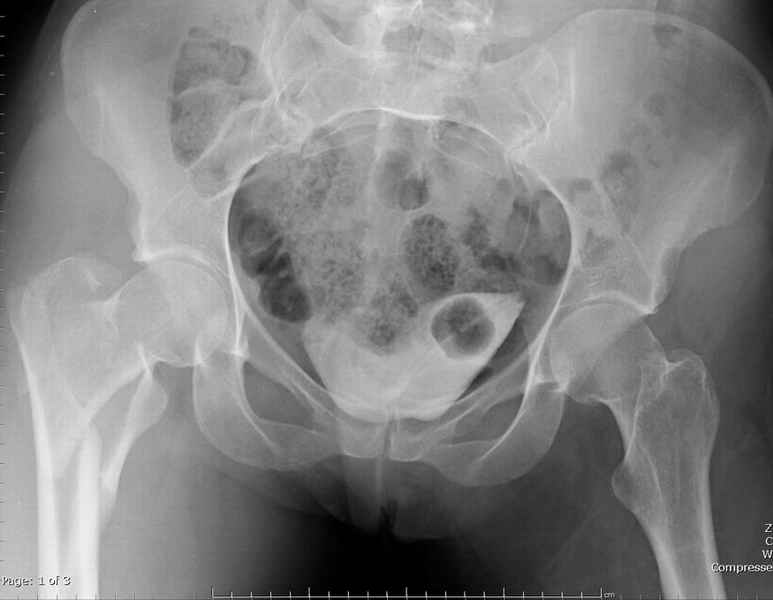

Ap pelvis Rt sub-intra trochanteric Fracture

Совершенно согласен с Mike, если у вас на очереди все представители компаний, предлагающие свои услуги, все методы хороши: пластины и шурупы, Compression Hip screw, Blade Plate, DCS, Intramedullary Nails:

Centromedullary and Cephalomedullary По классификация Seinsheimer

(1978) V- на основе количества фрагментов-нестабильный.

По Russel- Taylor Type II – Piriformis is not intact Type IIB – lesser

troch is not intact перелом с вовлечением двух кортексов и

вертела - нестабильный,

Ap pelvis Rt sub-intra trochanteric Fracture, AP Rt hip, Postop Blade Fixation